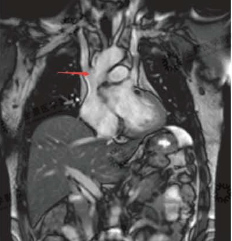

5. 大血管病变

MRI除了可以显示病变结构,如先天畸形、主动脉夹层的破口位置、累及范围等,还可以利用PC法进行血流测量,显示腔内血流在心动周期不同阶段的速率和方向,为正确、及时治疗提供形态学和功能学信息。